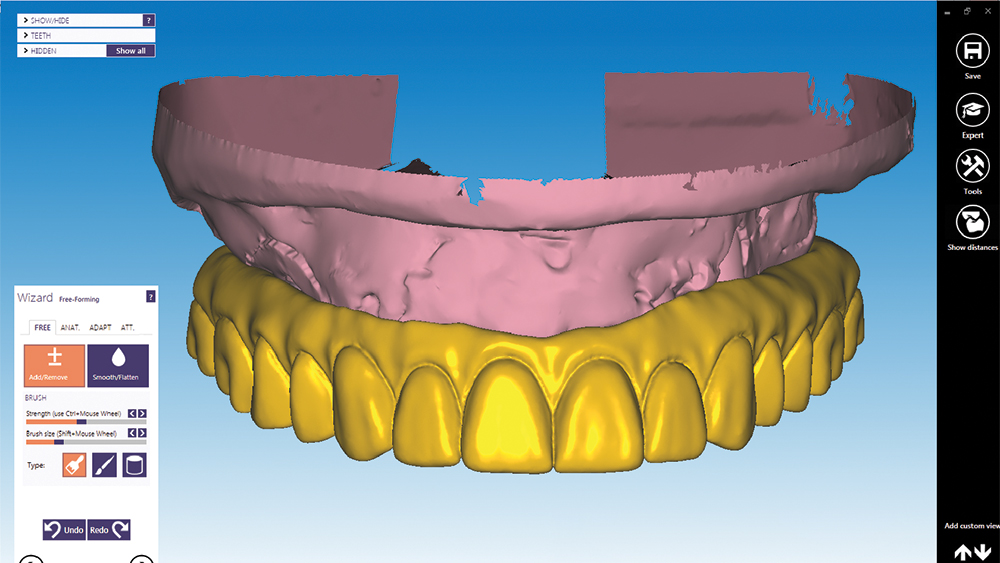

During the restorative phase of treatment, dentists are taking advantage of the CAD/CAM process to fine-tune prosthetic designs with a remarkable degree of precision, providing the patient with a confident smile. Clinicans can visualize the ideal prosthetic outcome through dental CAD software, confirm that design in physical form via the PMMA provisional implant prosthesis, and make any final adjustments before the final restoration is produced in durable, esthetic BruxZir® Solid Zirconia.

A patient sought treatment for advanced caries and periodontal disease in the maxillary arch, which had become painful and compromised her oral function. Although her remaining mandibular teeth also required replacement, she couldn’t afford to restore both arches at once and, like most patients, she placed a higher priority on her maxillary arch because of her esthetic needs. Following a discussion of treatment options, the patient requested a fixed restoration and was opposed to a removable appliance. At the surgical appointment, her maxillary teeth were extracted and Hahn™ Tapered Implants (Glidewell Direct; Irvine, Calif.) were placed. Sufficient primary stability was established for an immediate provisional appliance, which satisfied the patient’s request to leave the surgical appointment with a fixed restoration in place. After five months of healing and confirmation of the prosthetic design with a PMMA provisional, function, esthetics and quality of life were restored with a BruxZir Full-Arch Implant Prosthesis.